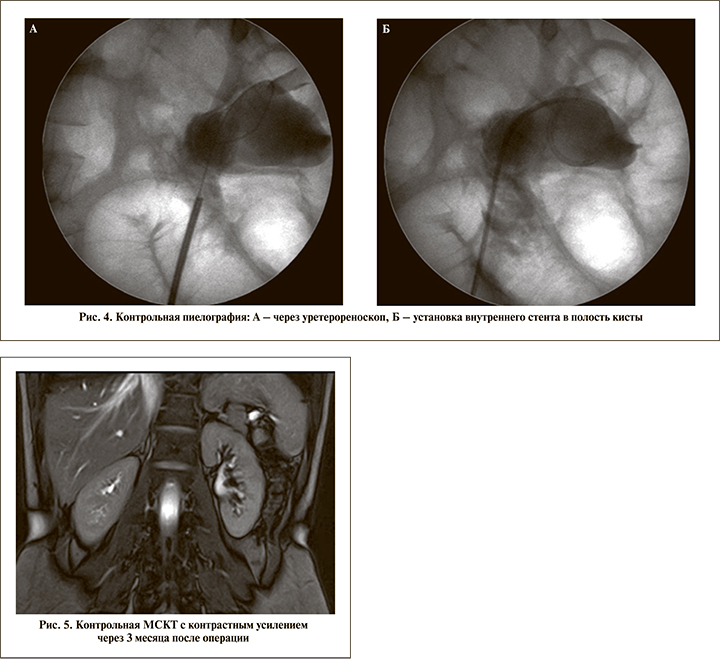

При трансуретральном доступе под эндотрахеальным наркозом вводился ригидный уретероренооскоп диаметром 8 Fr. Выполнялись уретерореноскопия, ретроградная пиелография, при необходимости использовалось интраоперационное УЗИ для уточнения локализации кисты и места рассечения ее стенки (3 пациента). В дальнейшем через рабочий канал проводилось лазерное волокно (365 мкм), выполнялся разрез выступающей в лоханку стенки кисты на всем протяжении и тщательно осматривалась ее полость в белом свете, а также с применением узкоспектровой эндоскопии (NBI-технология, Olympus) или компьютерной хромоэндоскопии (Image1S-технология, Karl Storz). При изменениях внутренней стенки кисты выполнялась «холодная» биопсия. Для дренирования полости кисты интраоперационно устанавливался внутренний мочеточниковый J-J-стент на срок от 4 до 6 нед. (рис. 1–5). При перкутанном доступе интраренальная лазерная марсупиализация парапельвикальной кисты выполнялась после выполнения нефролитотрипсии через нефроскоп диаметром 24 Fr. Помимо нефростомического дренажа пациентам в полость кисты антеградно устанавливался внутренний J-J-стент. Нефростомический дренаж удалялся на 2–3-и сутки после операции, внутренний стент – через 4–6 нед.

В дальнейшем всем пациентам проведено контрольное обследование в установленные сроки (3–30 мес.), которое включило МСКТ с контрастированием, а также УЗИ почек. Девяти пациентам во время удаления внутреннего стента выполнена контрольная смотровая уретерореноскопия.

В периоде наблюдения пациентам проводились МСКТ с контрастным усилением и УЗИ почек на 3-й и 12-й месяц после марсупиализации. По данным УЗИ расширения ЧЛС не отмечено ни у одного пациента, по данным МСКТ с контрастированием, только у одного пациента размер кисты которого составлял 4,9 см, отмечена резидуальная полость без признаков обструкции ЧЛС размером 2,4 см на 3-й месяц и 1,6 см на 12-й месяц наблюдения соответственно. Макрогематурия, которую отмечали пациенты до оперативного вмешательства, не рецидивировала.